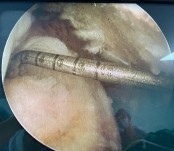

Đóng neo khâu theo, tiến hành tạo vi tổn thương tại diện bám CX qua nội soi theo kỹ thuật kỹ thuật phối hợp của nhóm tác giả Stephen J. Snyder và nhóm tác giả Guiseppe Milano, áp dụng một số đặc điểm nghiên cứu về KC giữa bờ ngoài diện bám và bờ sụn khớp để tính toán vị trí tạo vi tổn thương24,25:

- Sử dụng dùi nội soi đường kính khoảng 1,6mm, dùi này được đưa vào qua cổng vào thích hợp và được đặt vuông góc với vỏ xương cứng sau đấy đâm thủng và đi vào xương xốp. Tạo các lỗ vi tổn thương ở phía trong vị trí đặt neo, các lỗ này được đóng sâu khoảng 5mm hoặc đến khi nào thấy các giọt mỡ thoát ra là được.

- Dựa vào các chỉ số KC từ bờ ngoài diện bám gân CX mà cụ thể là từ điểm bờ trước ngoài gân trên gai, dưới gai, tròn bé đến bờ sụn khớp(từ 10,01 - 10,25- 12,8mm) so với bề mặt sụn khớp để tính toán vị trí tạo vi tổn thương sao cho KC giữa các lỗ khoảng từ 4-5 mm trở lên và không có quá một lỗ giữa hai neo chỉ sát nhau (trong trường hợp khâu từ 2 neo trở lên) để tránh nguy cơ yếu neo chỉ. Chúng tôi thường tạo vi tổn thương theo 2 hàng với vị trí hàng tạo vi tổn thương đầu tiên sát rìa sụn khớp, hàng thứ 2 tiếp theo vị trí ở phía ngoài so với hàng thứ nhất 5mm và vị trí các lỗ vi tổn thương đan xen với hàng đầu tiên.

Hình 2.22. Hình minh hoạ cách tạo lỗ vi tổn thương theo hàng phía trong vị trí đặt neo

- Để thuận tiện cho quá trình tạo vi tổn thương chúng tôi tạo dụng cụ dùng để tạo vi tổn thương có cấu tạo giồng kiểu compa. Dụng cụ này gồm 1 phần cố định (chân compa) hàn gắn cố định với 1 ống rỗng có lòng đường